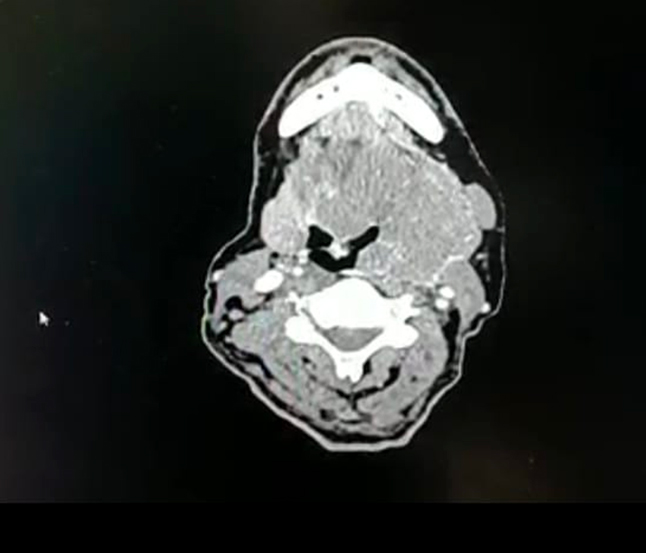

CECT Neck Axial cut showed heterogenously enhancing lesion occupying left parapharyngeal space, medially pushing the airway and laterally reaching till parotid and posteriorly till retropharyngeal space. Anteriorly it extended till retromolar trigone, involving left vallecula and inferiorly it reaches just below hyoid bone (Figure 2)

Figure 2. CECT Neck Axial Cut showing lesion occupying Parapharyngeal Space